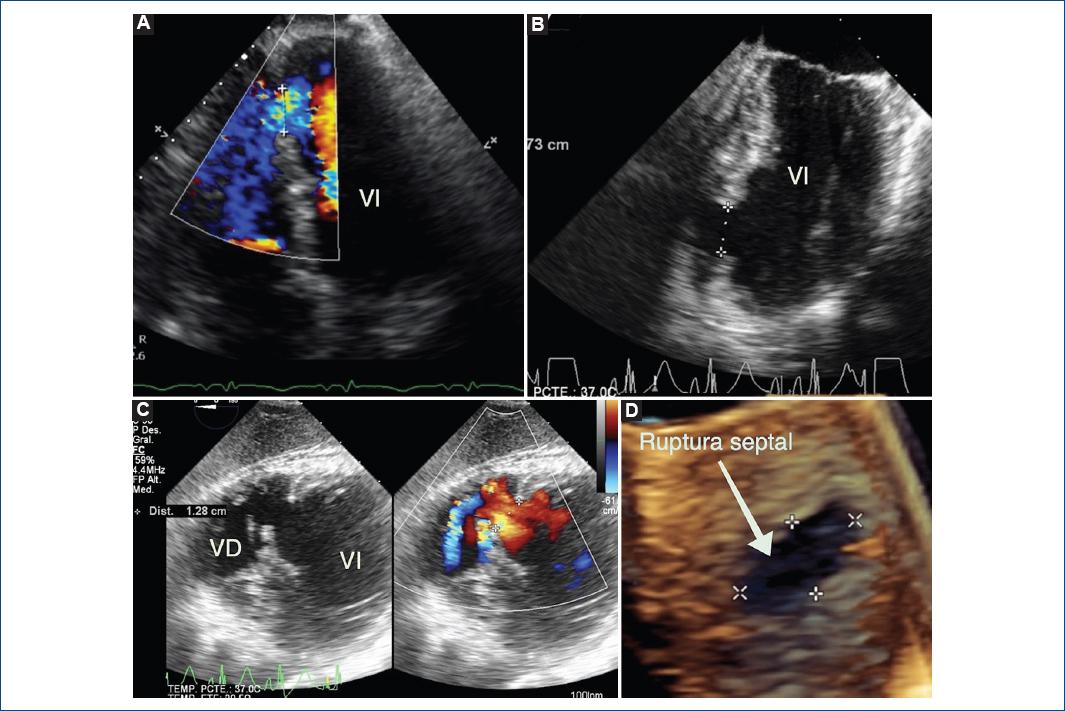

Figura 3 A: Ecocardiograma transtorácico bidimensional y con Doppler a color en el plano apical de cuatro cámaras, que muestra ruptura septal en la porción apical del septum. B: Ecocardiograma transesofágico bidimensional que muestra la ruptura septal en la porción apical del septum. C: Ecocardiograma transgástrico bidimensional y con Doppler a color, a nivel de ambos ventrículos, que muestra la ruptura septal. D: Reconstrucción tridimensional de la ruptura septal que tiene forma ovalada (flecha blanca).

Paciente masculino de 46 años de edad con antecedentes personales de hipertensión arterial sistémica, tabaquismo y etilismo y heredofamiliares de hipertensión arterial sistémica. El padecimiento inició con cuadro de astenia, adinamia, disnea progresiva, edema de miembros inferiores y aumento del volumen abdominal, por lo que acudió con el médico, quien decidió hospitalizarlo. El paciente recibió tratamiento médico con captopril, furosemida y espironolactona, sin mejoría de los síntomas, motivo por el cual fue referido a la institución. Al llegar al servicio de urgencias, el sujeto se encontraba estable. A la exploración física estaba consciente y orientado, con adecuada coloración e hidratación de tegumentos, ingurgitación yugular grado II y pulsos carotídeos simétricos de adecuada amplitud. La auscultación reveló estertores crepitantes en la región subescapular bilateral, hipoventilación en la región subescapular derecha y síndrome de derrame ipsilateral. El choque de la punta se palpó en el sexto espacio intercostal, línea media clavicular izquierda y se detectó frémito paraesternal izquierdo. Los ruidos cardíacos eran rítmicos, con S3 y soplo holosistólico en mesocardio III/IV, con irradiación excéntrica y sin frote pericárdico. Las extremidades inferiores estaban íntegras, simétricas, con edema hasta el tercio proximal tibial bilateral y llenado capilar inmediato. Los pulsos eran simétricos y de adecuada amplitud en las cuatro extremidades. El electrocardiograma mostró ritmo sinusal con FC de 83 lpm, dextrorrotación, crecimiento de la aurícula izquierda e imagen de infarto reciente inferolateral, con onda q, lesión subepicardica e inversión simétrica de la onda T en DII, III, aVF, V5 y V6 (Fig. 1). En la radiografía de tórax se observó cardiomegalia grado II con hipertensión venocapilar pulmonar (Fig. 2). El ecocardiograma demostró ruptura septal apical de 17 mm (Fig. 3), con Qp/Qs de 3.6 y gradiente a través del defecto de 26 mmHg y presión sistólica de arteria pulmonar de 74 mmHg (Fig. 4), dilatación auricular izquierda y función sistólica del ventrículo izquierdo normal, con fracción de expulsión de 58%. El paciente ingresó a la sala de hemodinámica para colocación de un balón intraaórtico de contrapulsación (BIAC). Se realizó coronariografía diagnóstica, que demostró tronco, arteria descendente anterior izquierda y circunfleja sin lesiones angiográficas significativas, con flujo distal TIMI 3. La arteria coronaria derecha dominante mostraba lesión tubular ulcerada en el segmento medio, de bordes mal definidos, excéntrica, con sitio de máxima estenosis del 70% y oclusión total crónica de la descendente posterior en el segmento medio (flujo TIMI 0), con circulación colateral de la arteria descendente anterior, Rentrop 3 (Fig. 5). En la ventriculografía se identificó una comunicación interventricular apical y la presión teledistólica del ventrículo izquierdo fue de 35 mmHg. Se inició tratamiento con diurético de asa, nitroprusiato de sodio y levosimendán a dosis-respuesta, con evidente mejoría. Se colocó un catéter de Swan-Ganz, que demostró una presión capilar pulmonar de 34 mmHg.